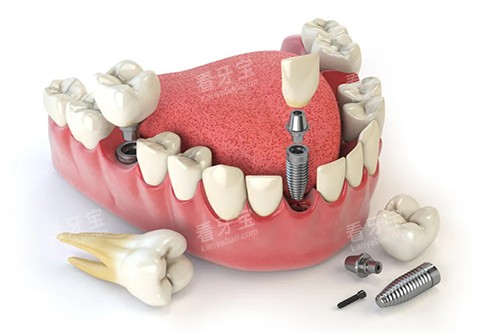

精密种植技术

西安双宝口腔采用的精密种植技术是其种牙技术的一大亮点。

通过口腔 CT 扫描仪,医生可以获取患者口腔的三维影像数据,清晰地了解牙槽骨的密度、高度、宽度等情况,从而精密地确定种植体的植入位置、角度和深度。

这种精密的种植技术大大提高了种植手术的可行性,减少了手术创伤和并发症的发生。

例如,对于一些牙槽骨条件较差的患者,医生可以根据精密的影像数据,制定个性化的骨增量方案,为种植体的植入创造良好的条件。